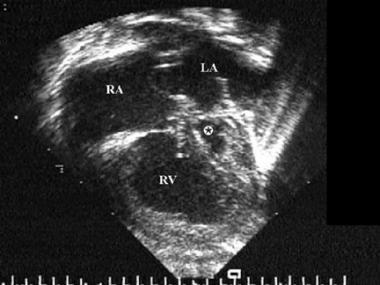

Doctors often use echocardiography to diagnose hypoplastic left heart syndrome. The test uses sound waves to create a moving picture of your baby that can be viewed on a monitor.

If your baby has hypoplastic left heart syndrome, an echocardiogram will show abnormalities. For example, the left ventricle and aorta will be smaller than normal. In addition, echocardiography also showed abnormalities of the heart valves.

Because the test can monitor blood flow, it also shows flow from the right ventricle into the aorta. In addition, echocardiography can identify associated heart defects. The malformation mentioned may be an atrial septal defect.